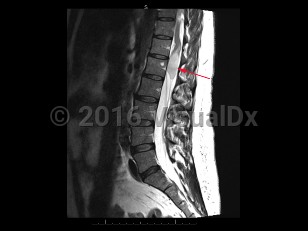

Cauda equina syndrome

Cauda equina syndrome is a neurologic emergency where damage to the lumbosacral plexus leads to loss of lower motor neuron function. Trauma, tumors or abscesses, large lumbar disk herniation, and spinal stenosis are some of the etiologies of this condition.

Onset is typically gradual but can be acute. Signs and symptoms include severe back pain that may radiate into one or both legs, saddle anesthesia, leg weakness or paraplegia, urinary or bowel dysfunction, sexual dysfunction, and gait disturbance. There may be reduced or absent patellar, Achilles, anal, and bulbocavernosus reflexes.

Prognosis depends on severity and duration of compression or damage to the affected nerves.